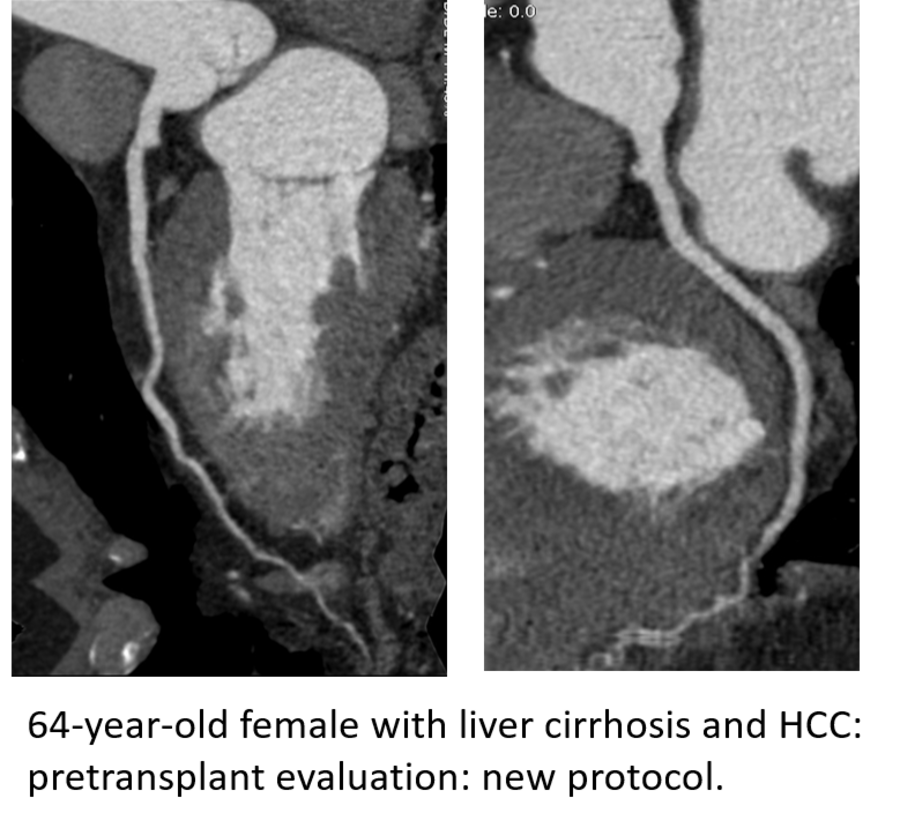

Pre-transplant liver and renal patients: The pre-transplant patients require coronary artery imaging to assess the risk of cardiac ischemia before major surgery such as the solid organ transplant. Unfortunately, standard coronary CTA imaging protocols yield suboptimal image quality in these patients due to their altered hemodynamic status. This results in either a suboptimal assessment of their pre-transplant risk or a need for invasive (and hence risky) imaging protocols such as coronary catheterization.

1. Pre-liver transplant patients usually have low ejection fraction, large extracellular space, and portosystemic shunting. Thus, we implemented a protocol with increased IV contrast volume and injection rate in combination with decreased kVp to increase vessel enhancement.